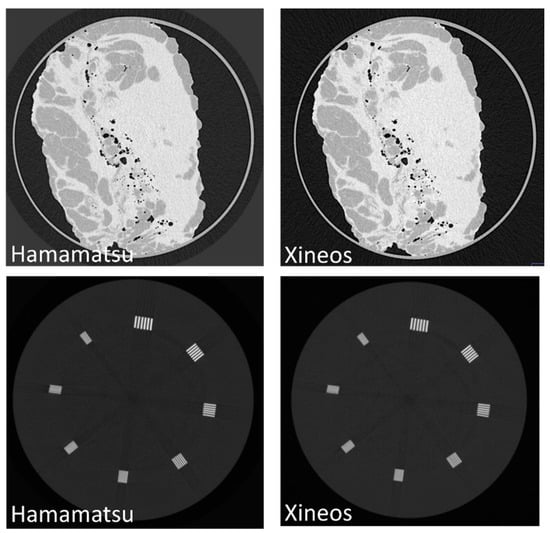

| Hamamatsu | Xineos | |

| Number of pixels | 1216 × 1232 | 2097 × 2111 |

| Pixel size | 100 µm | 99 μm |

| Exposure time | 59 ms | 25 ms |

| Frame rate | 17 fps | 40 fps |

| Max counts | 4000 (12-bit) | 16,000 (14-bit) |

| Acquisition mode | Fine mode | Mag1 (70%) |

| xres (µm) | 152 ± 9 | 169 ± 7 | 147 ± 4 | 164 ± 2 |

| yres (µm) | 172 ± 11 | 183 ± 7 | 175 ± 6 | 186 ± 5 |

| SNR | 6.0 ± 0.6 | 7.6 ± 0.5 | 7.4 ± 0.9 | 9.3 ± 0.3 |

| SNR/res (µm−1) | 0.037 ± 0.004 | 0.043 ± 0.002 | 0.046 ± 0.006 | 0.053 ± 0.002 |